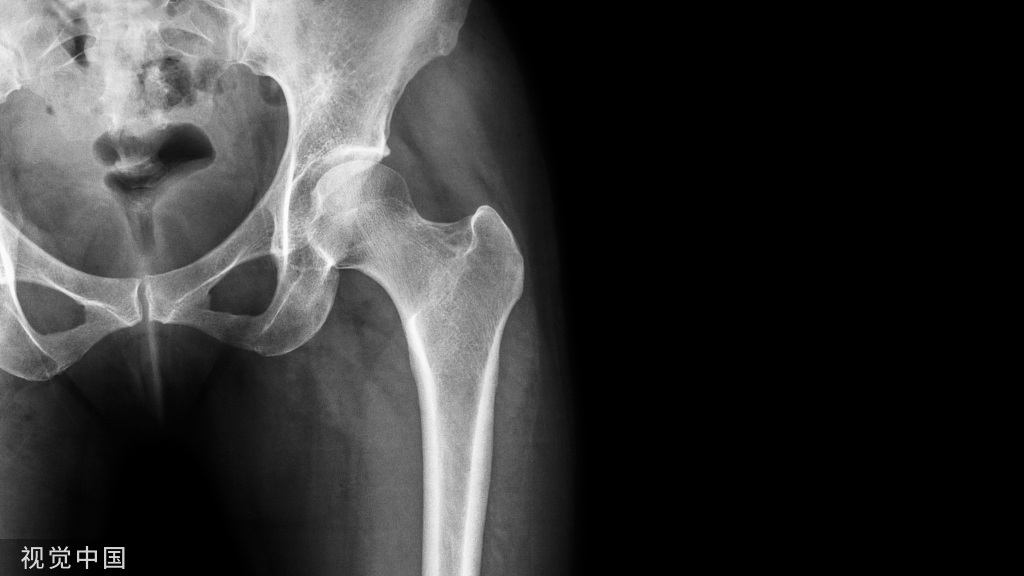

再如案例2:

病人施行的是进口全陶瓷髋关节置换术,术后诉术侧延长2cm,行走特别不舒服,进行康复治疗较长时间亦无明显改善;尽管从影像看双下肢等长——却改变了髋关节解剖(旋转中心上移、略内翻)。